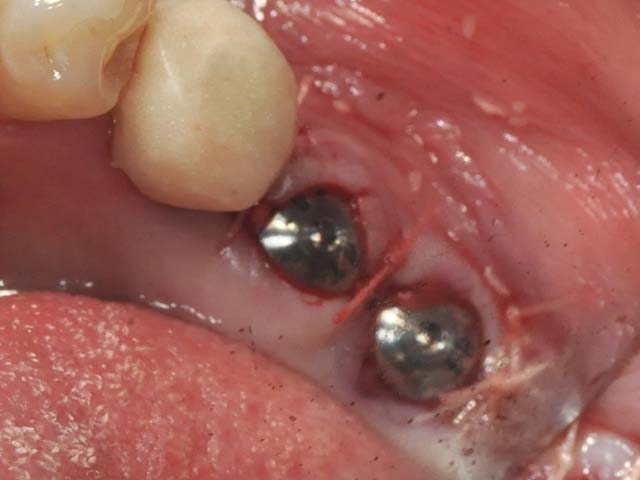

牙橋嚴重蛀牙,即拔即種,避免二次傷口 首頁 案例分享 人工植牙 牙橋嚴重蛀牙,即拔即種,避免二次傷口 多年前製作之牙橋,因為二度齲齒,導致支台齒蛀蝕,而需重新製作 牙橋支臺齒嚴重蛀牙 STEP1.拔除殘根並植入兩根植牙 STEP2.骨粉填補缺損骨頭缺陷 STEP3.三個月後,準備製作正式假牙 STEP4.正式假牙完成